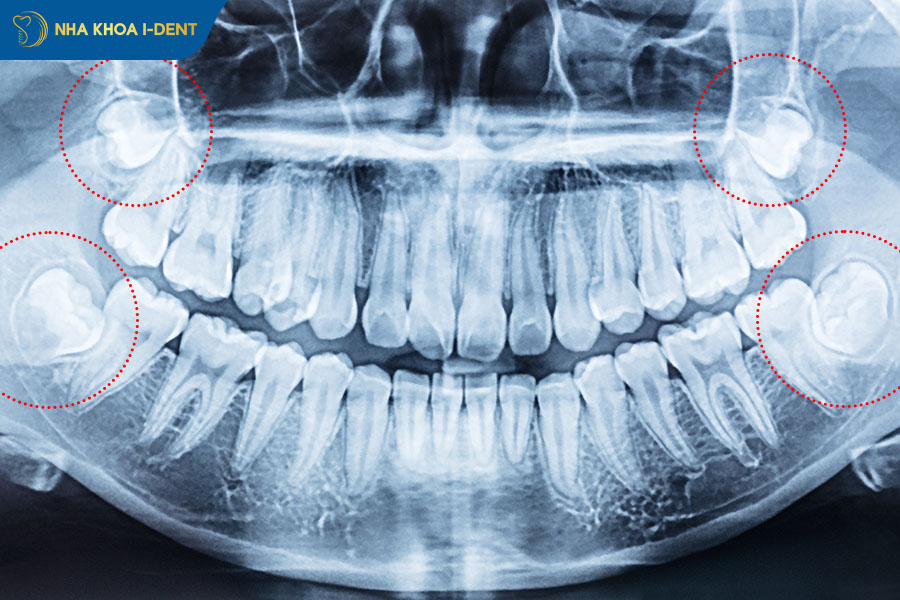

Trong những trường hợp này, Hiệp hội Nha khoa Mỹ (ADA) cho phép theo dõi định kỳ thay vì nhổ ngay. Tuy nhiên, cần lưu ý: tình trạng răng có thể thay đổi theo thời gian, đặc biệt sau tuổi 30 khi xương hàm cứng hơn và khả năng điều chỉnh vị trí giảm đi. Vì vậy, dù không nhổ, bạn vẫn cần chụp X-quang kiểm tra định kỳ 6–12 tháng một lần để phát hiện sớm bất kỳ thay đổi nào.

- X-quang phát hiện chân răng số 7 đang bị chèn ép, mất xương xung quanh thân răng số 8, hoặc hình ảnh bóng mờ bất thường (nghi u nang).